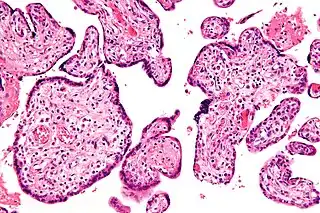

Histopatología

Histomorfológicamente, la VUE se caracteriza por un infiltrado linfocitario de las vellosidades coriónicas sin una causa demostrable. Las células plasmáticas deben estar ausentes; la presencia de células plasmáticas sugiere una etiología infecciosa, por ejemplo, infección por CMV.